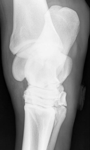

• Lateromedial radiographic projection of the right hock of a mature horse showing osteophyte formation and narrowing of the distal intertarsal joint

• Oblique radiographic projection of the same hock showing marked osseous reaction and narrowing of the distal intertarsal joint

Hindlimb lameness is a common occurrence in equids of all shapes, sizes and athletic disciplines. Not only does it have welfare implications for the horse, it is also a performance limiting factor and a source of economic loss. Once identified it may present a diagnostic challenge to veterinary surgeons when trying to pinpoint the source of pain. There are a multitude of orthopaedic conditions affecting the equine hindlimb, which may affect any soft tissue or bony structure from the distal phalanx to the pelvis. This article focuses on osteoarthritis of the small hock joints as one of the more common causes of hindlimb lameness.

Radiographic examination of the tarsus may be conducted, generally four views are required as in some cases lesions may only be present in one radiographic view. Images of both hocks should be obtained as disease is often bilateral. Classical radiographic signs of OA include narrowing of the joint spaces, peri-articular osteophyte formation and in more advanced cases, lysis or sclerosis of the subchondral bone underlying the cartilage. There appears to be a poor correlation between the extent of radiographic abnormality and the degree of lameness, for instance sometimes a horse with subtle radiographic signs of OA may appear more painful than the horse with advanced disease whereby the small tarsal joints are almost fused together. Additional diagnostic aids such as ultrasonography or nuclear scintigraphy may be employed if radiographic examination is inconclusive.